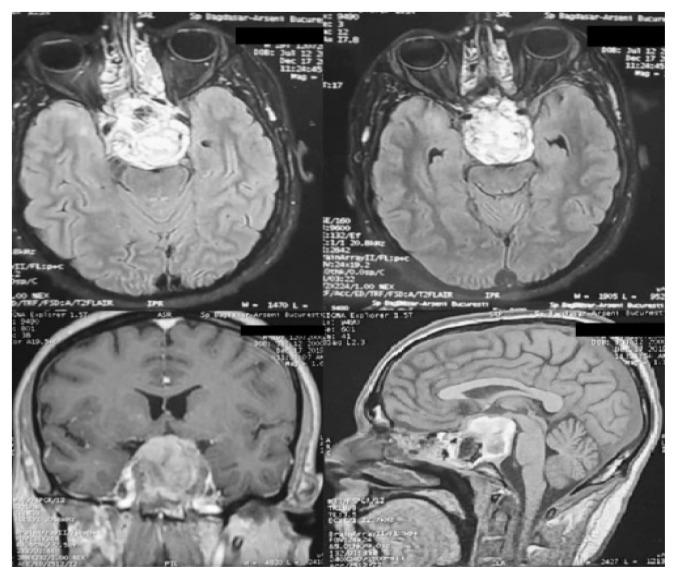

There were 6 males and 9 women, mean age 52.8 ± 16.55 years. Tumor site was clivus (13 patients), left cavernous sinus (one case) and sphenoidal sinus (one case). We performed endoscopic endonasal approach (18 times), transcranial subtemporal approach and combined approach. We achieved GTR in 8 patients, NTR in 4 patients, STR in 7 patients and biopsy in 1 patient. Grade of resection was associated with recurrence incidence (p=0.002).Histological exam revealed conventional chordoma in 14 cases, chondroid chordoma in 5 cases and dedifferentiated (chondrosarcoma) in 1 case. Patients' neurological status improved following surgery (p=0.000). Five patients underwent adjuvant conventional radiotherapy.Five patients presented local recurrence. All recurrences were reoperated using endoscopic endonasal approach. Survival analysis identified grade of resection and adjuvant radiotherapy as predictive factors for recurrence-free survival.

男性6例,女性9例,平均年龄52.8±16.55岁。肿瘤部位为斜坡(13例)、左侧海绵窦(1例)和蝶窦(1例)。我们采用了鼻内镜经鼻入路(18次)、经颞下入路及联合入路。8例患者实现了全切除(GTR),4例次全切除(NTR),7例次次全切除(STR),1例患者仅行活检。切除程度与复发率相关(p=0.002)。组织学检查显示14例为传统型脊索瘤,5例为软骨样脊索瘤,1例为去分化型(软骨肉瘤)。患者术后神经功能状态改善(p=0.000)。5例患者接受了辅助性常规放疗。5例患者出现局部复发。所有复发病例均采用鼻内镜经鼻入路再次手术。生存分析确定切除程度和辅助放疗是无复发生存的预测因素。